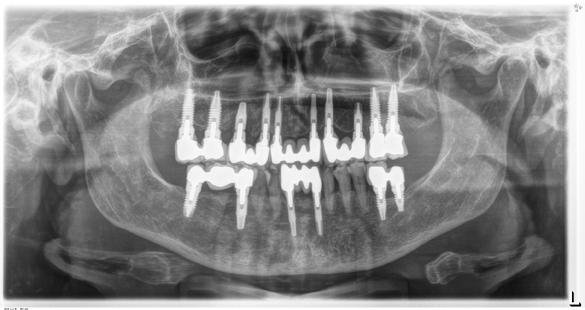

Figura 1. Radiografía inicial de la paciente. Se observa edentulismo total superior, a excepción del molar del primer cuadrante, indicado para exodoncia. En la mandíbula se aprecia pérdida ósea horizontal generalizada secundaria a la evolución de la enfermedad periodontal.

Figura 3. Radiografía tras la colocación de los implantes superiores e inferiores y la carga inmediata del sector anterosuperior.

En la radiografía inicial (Figura 1) se observa la pieza 17 con pérdida ósea significativa, así como una reabsorción ósea homogénea a lo largo de todo el arco superior. En la arcada inferior se aprecia pérdida ósea horizontal generalizada y defectos localizados, como una lesión en cuña en la pieza 46. Ante esta situación, se decide realizar la exodoncia del molar remanente del

arco superior y planificar una rehabilitación implantosoportada para todo el maxilar superior, así como para el extremo distal del tercer cuadrante.

En los cortes del cone-beam de planificación se observa la posibilidad de colocar implantes estrechos en la zona anterior del maxilar, así como implantes de mayor diámetro y longitud en los sectores posteriores (Figura 2).

En el extremo libre del tercer cuadrante es posible la colocación de implantes sin técnicas accesorias, ya que existe volumen óseo suficiente. Es importante señalar que la planificación de este caso se realizó hace 25 años, cuando

Figura 12. Radiografía final con la prótesis cementada en posición.

El mantenimiento periodontal y la implicación de la paciente en las medidas de autocuidado se mantuvieron de forma constante durante 23 años (Figura 25). La ortopantomografía realizada en una de las visitas de control mostró estabilidad completa de los implantes, sin signos radiográficos de pérdida ósea patológica.

Figura 21. Radiografía con la rehabilitación finalizada.

Figura 24. Radiografía a los 5 años que evidencia estabilidad ósea periimplantaria y periodontal.

25. Radiografía a los 25 años con mantenimiento del nivel óseo en implantes y dientes remanentes.